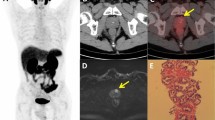

Patients randomly allocated to the PREVENT trial’s TP vs. TR PNB comparison were eligible for study. Informed consent was obtained from all subjects. The first efficacy results from this comparison have been published previously [12]. Briefly, from March 2021 through May 2023, patients were recruited at ten centers and were eligible for enrollment if they had not undergone prior PNB, had an elevated PSA level and/or abnormal digital rectal examination (DRE), and had suspicious prostate magnetic resonance imaging (MRI) characteristics (Prostate Imaging Reporting and Data System, version 2.1 [13] scores 3–5). They were then randomized 1:1 to TP PNB without antibiotic prophylaxis or TR PNB with targeted antibiotic prophylaxis. All patients underwent multiparametric MRI (mpMRI) per study protocol prior to enrollment and randomization. mpMRI protocols had slight variation by study site but all included T1 and T2 weighted sequences with diffusion-weighted imaging and dynamic contrast enhancement series. Reviewers were blinded to treatment allocation and outcomes as previously reported [12]. A small number of participants had biopsy without MRI (claustrophobia and metal prosthesis) and were included in the original trial but were excluded from this secondary analysis as the primary outcome of this analysis is predicated on presence or absence of mpMRI PI-RADS lesions. The exclusion criteria were acute prostatitis in the last 6 months or any current bacterial infection requiring antibiotic treatment. All patients provided written informed consent. The trial is registered at ClinicalTrials.gov (NCT04843566), funded by the NCI (5R01CA241758-05) and had full regulatory, national ethics committee, and local site approval. Full details of the PREVENT trial protocol is provided in Supplementary Methods 1. As part of the trial, race data was collected via self-reporting and used for this secondary analysis.

When assessing for cancer detection, there was a statistically significant increase in rates of overall PCa (70% vs. 43%%, P = 0.004) (Fig. 1) and csPCa (60% vs. 27%, P = 0.003) for Black patients with PI-RADS 3 lesions compared to White patients (Fig. 2) (Table 2). On logistic regression controlling for age, biopsy approach, and PSAD, Black men with PI-RADS 3 or 4 lesions had higher odds of overall PCa (OR 1.17, P = 0.009) and csPCa (OR 1.20, P = 0.004) detection than White men with PI-RADS 3 or 4 lesions (Table 3).

For Asian men, there was a statistically significant decrease in rates of overall PCa (0% vs. 47%, P = 0.004) (Fig. 1) and csPCA (0% vs. 27%, P = 0.003) (Fig. 2) (Table 2). On logistic regression controlling for age, biopsy approach, and PSAD, Asian men with PI-RADS 3 or 4 lesions had lower odds of overall PCa (OR 0.79, P = 0.01) but not csPCa (OR 0.94, P = 0.5) than White men with PI-RADS 3 or 4 lesions (Table 3).